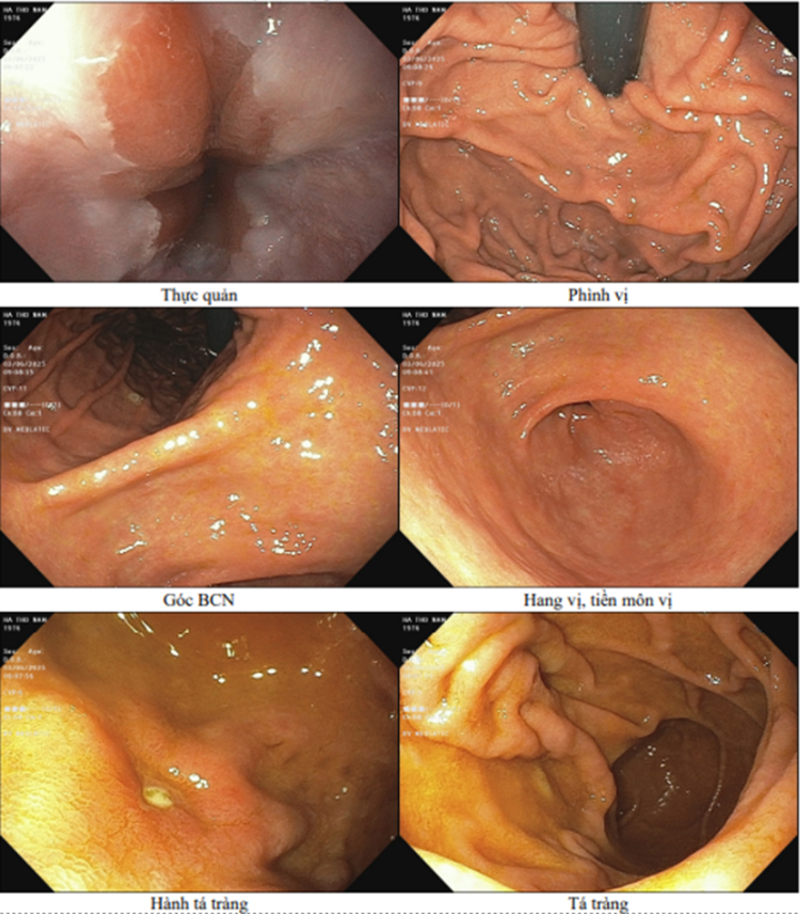

Kết quả nội soi tiêu hóa của bệnh nhân

Nội soi tiêu hóa cho kết quả viêm dạ dày.